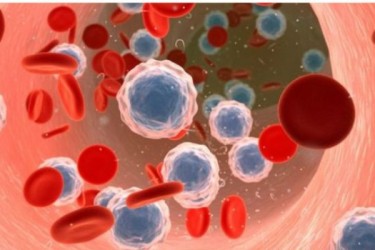

ক্যানসার চিকিৎসায় সাফল্যের দ্বারপ্রান্তে বিজ্ঞানীরা

প্রাণঘাতী ক্যানসার রোগের চিকিৎসায় বৈপ্লবিক পরিবর্তন নিয়ে আসতে পারে, এমন এক চিকিৎসা-পদ্ধতি আবিষ্কারের দ্বারপ্রান্তে পৌঁছে গেছেন বিজ্ঞানীরা। মঙ্গলবার বিবিসি অনলাইনের এক ..বিস্তারিত